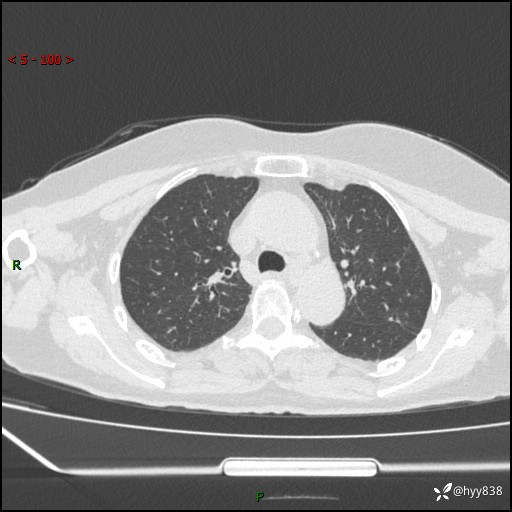

老年女性,偶然发现肺结节10天。结节不大,空洞不小,还牵拉胸膜---结果公布~

现病史:患者10余天前因“左侧鼻塞伴鼻腔异味2月”就诊于我院耳鼻喉科,查胸部CT示:左上肺结节影,建议复查。患者偶有咳嗽、咳痰,多咳白痰,无畏寒、发热,无胸痛、呼吸困难等,现为进一步明确肺结节性质,就诊于我科门诊。现以“孤立性肺结节”收住我科。 起病来,患者精神、食欲、睡眠尚可,体力、体重无明显变化。

胸部CT(2024.7.16)